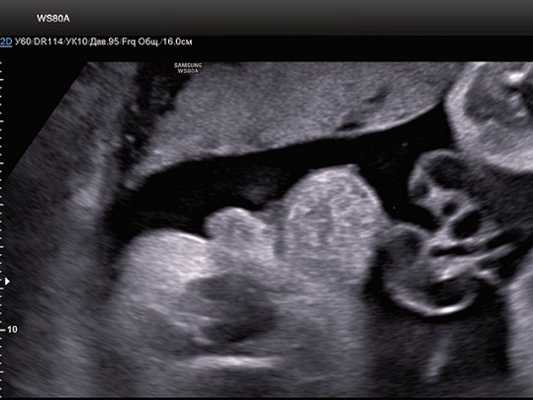

При УЗ-исследовании обнаружен один живой плод женского пола в головном предлежании. Гестационный срок составил 34,4 нед. Фетометрические показатели плода соответствовали данному сроку. Патологических изменений плаценты и околоплодных вод не выявлено. При исследовании мочевой пузырь в типичном месте не визуализировался.

В нижних отделах передней брюшной стенки в надлобковой области визуализировалось эхогенное образование размером 30x28x25 мм (рис. 1, 2). Определялось низкое впадение пуповины. Почки плода визуализировались в типичном месте, без структурных изменений. Патологических изменений других органов не было выявлено.

Рис. 1. Эхогенное образование в нижнем отделе передней брюшной стенки (экстрофированный мочевой пузырь).

Рис. 2. Экстрофия мочевого пузыря в сочетании с отсутствием видимой патологии наружных половых органов (режим трехмерной реконструкции).

Поставлен диагноз: "Беременность 34,4 нед. ВПР плода - экстрофия мочевого пузыря".